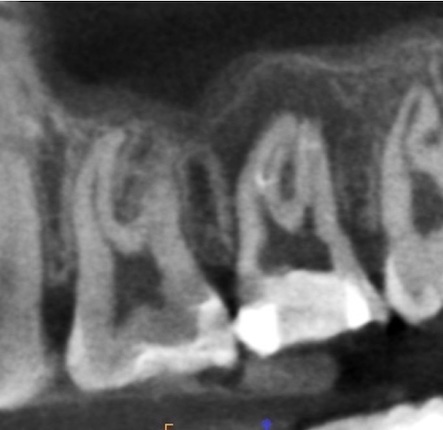

かぶせ物が不適であること(青矢印部)、近心根に根尖病巣があること(青枠部)、根充剤がかなり太いため(赤矢印部)歯質が薄くなっていることなど問題点がいくつかありましたが、他院で治療をしたばかりであり、また上記の条件から再治療には抜歯のリスクが非常に高いことから初診時は患者さんと相談し経過観察することになりました。